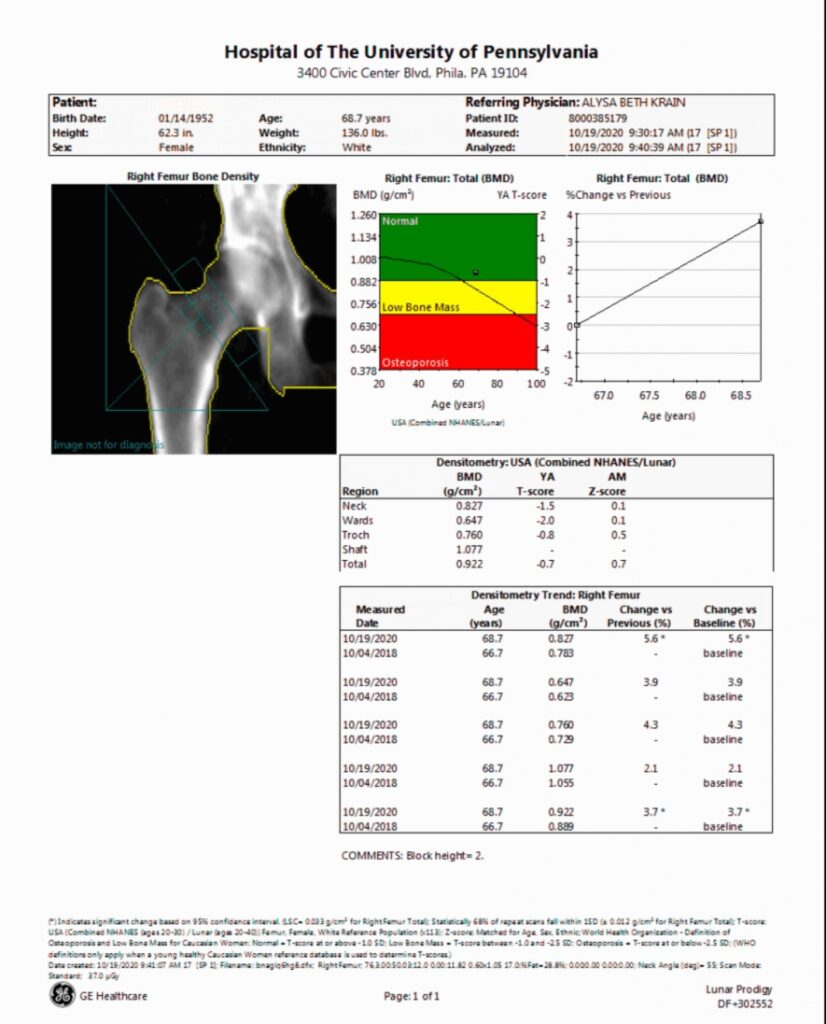

DEXA Scan

img01

Prodigy DXA systems help enhance your patient care and practice workflow with the following benefits:

• Bone Mineral Density (BMD) assessment to help with diagnosing osteoporosis

• Optional Integrated Trabecular Bone Score (TBS), Advanced Hip Assessment, FRAX and other tools can aid in assessing borderline cases

• Measurement of lean and fat-tissue mass, including percentage of fat, for body composition assessment and to help with understanding metabolic health risk

• Streamlined patient care with applications for faster scanning and less dose

• Improved practice workflow with customizable and easy-to-use reporting